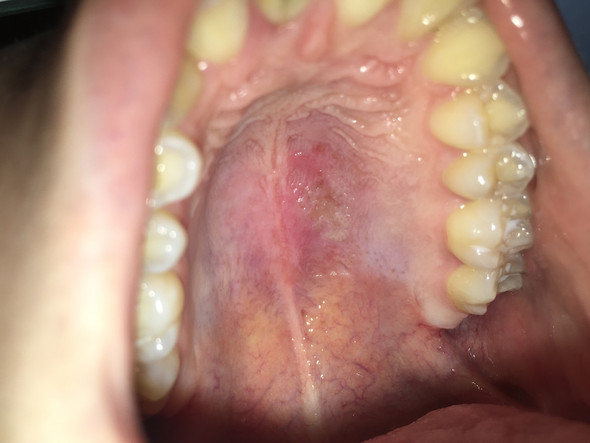

Offene stelle am gaumen. Sie haben ein zu hartes Brötchen mit Kanten und schon ist es passiert die Haut und weiteres Gewebe werden im Mundraum verletzt. Die Heizungsluft trocknet die Lippen aus mit der Zahnseide hat man sich das Zahnfleisch verletzt oder es kribbelt schon wieder ein Herpesbläschen eine kleine Wunde im Mund entsteht schnell. Einer Woche eine offene Stelle am Gaumen direkt hinter den Zähnen.

Offene stelle am gaumen hallo ich habe seit ca. Auf welche Symptome Sie achten sollten und mit welchen. Diese kann aufgrund von Verletzungen Infektionen allergischen Reaktionen oder gar Verbrennungen auftreten.

Diese wird genau untersucht. Eine Entzündung am Gaumen fällt meist durch eine schmerzhafte Schwelllung und Rötung auf. Beschwerden am gaumen bei zahnschmerzen hintergrund können zahnschmerzen sein die sich auf den gesamten mund rachen bereich ausdehnen und damit auch den gaumen betreffen können einleitung eine entzündung am gaumen fällt meist durch eine schmerzhafte schwelllung und rötung auf.

Recurrent aphthous stomatitis oral apthous ulcers sind kleine weiße oder rote offene Stellen oder Geschwüre der Mundschleimhaut der Zunge oder des Gaumens. Die sorgt dafür dass aus dem Zucker im Honig Wasserstoffperoxid. Entzündung am Gaumen - Dr-Gumpert. Diese kann aufgrund von Verletzungen Infektionen allergischen Reaktionen oder gar Verbrennungen auftreten. Eine Entzündung am Gaumen fällt meist durch eine schmerzhafte Schwelllung und Rötung auf. Beschwerden am Gaumen bei Zahnschmerzen Hintergrund können Zahnschmerzen sein die sich auf den gesamten Mund-Rachen-Bereich ausdehnen und damit auch den Gaumen betreffen können Einleitung Eine Entzündung am Gaumen fällt meist durch eine schmerzhafte Schwelllung und Rötung aufDiese kann aufgrund von Verletzungen Infektionen allergischen. Ich hoffe ich bin im richtigen Forum. Der Begriff kommt aus dem Griechischen und bedeutet Schwämmchen. Beim Kauen oder bei Kontakt mit Fruchtsäure.

Hallo ich habe seit ca. Offene stelle am gaumen was tun Gaumenschmerzen. Eine Entzündung am Gaumen fällt meist durch eine schmerzhafte Schwelllung und Rötung auf. Zu diesem Zweck eignen sich Kräuter wie Johanniskraut Kamille Lindenblüten und Nelken die zu einem Tee zubereitet werden. Beim Kauen oder bei Kontakt mit Fruchtsäure. Eine leichte Gaumenreizung kann man schon von zu heißen Nahrungsmitteln bekommen. Aphthen sind eine der häufigsten Krankheiten der Mundschleimhaut.